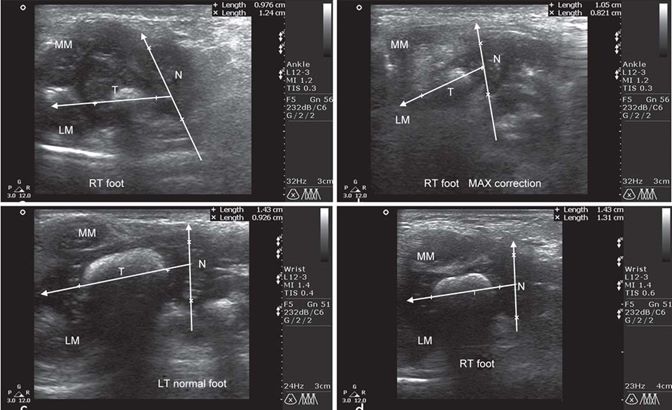

The radiologist was unaware of the clinical significance of the foot. Depending on the size of the foot, two linear probes of 26 and 45 mm were employed. The talonavicular angle of the deformed foot (Test, fig. 3A) and contralateral normal foot (Control, fig. 3C) was measured by drawing lines down the long axis of the talus and navicular bone on sonographic images. TNA changed during simulated Ponseti manipulation with the greatest possible foot abduction (fig. 3B).

Fig. 3: (A) Initial TNA in static position as measured sonographically, (B) change in TNA on simulated Ponseti manipulation by abducting the forefoot). The reducibility of navicular bone indicates about the flexibility of clubfoot, (C) TNA of the contralateral normal foot and (D) TNA at final correction showing sonographic correction as well